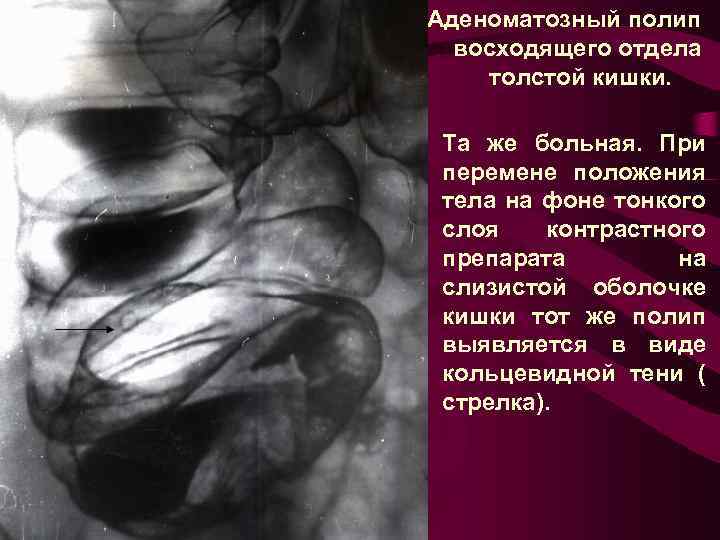

Аденоматозный полип восходящего отдела толстой кишки. Та же больная. При перемене положения тела на фоне тонкого слоя контрастного препарата на слизистой оболочке кишки тот же полип выявляется в виде кольцевидной тени ( стрелка).